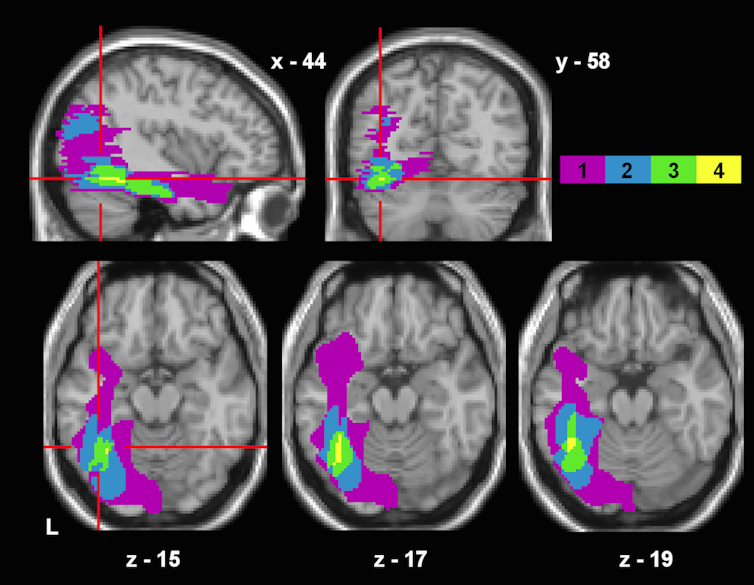

Evidence from functional brain imaging has led to the idea of a brain area that is specialised in recognising words and letters, called the “visual word form area”. It is this area that is commonly damaged in pure alexia. However, the role of this area in the way we read is highly debated and there is disagreement about whether it is reading-specific, or important for all sorts of visual recognition, such as looking at images or even faces. The same questions are discussed regarding pure alexia: whether the disorder is specific to reading or a more general deficit in somebody’s visual processing ability.

In most, if not all cases of pure alexia, other visual perceptual functions such as recognition of numbers or objects are affected, while other language functions, like speech comprehension and production – as well as writing – may be intact.